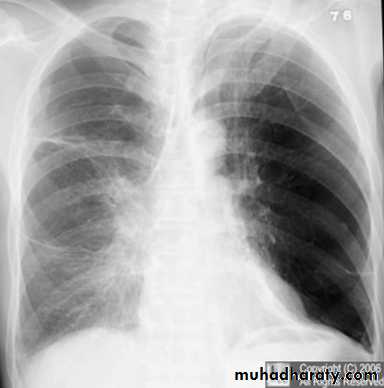

On a posteroanterior chest x-ray (A), the left hemithorax is very dark or lucent because the left lung has collapsed completely (white arrows).The tension pneumothorax can be identified because the mediastinal contents, including the heart, are shifted toward the right, and the left hemidiaphragm is flattened and depressed. A computed tomography scan done on a different patient with a tension pneumothorax (B) shows a completely collapsed right lung (arrows) and shift of the mediastinal contents to the left.

Tension Pneumothorax. Portable chest film in a 43-year-old woman with ARDS shows a large right pneumothorax with mediastinal shift and ipsilateral diaphragmatic depression, suggesting tension.

Air was evacuated under pressure during emergent placement of a right chest tube.